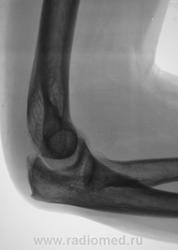

Внутренний вывих?

+ разрыв проксимального луче-локтевого сочления

Вроде бы и добавит нечего, кроме шпоры локтевого отростка.

чет то не встало на место (антирепозиция -депозиция) - стало хуже ((( - надо переделать..

Никак не разгляжу - перелом плеча патологический, на фоне литического очага, или мне кажется?

Просто сложный рельеф перелома.